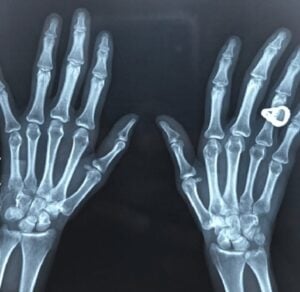

En Suède, une véritable révolution technologique est en marche : de plus en plus de citoyens choisissent volontairement de se faire implanter une puce électronique sous la peau, généralement entre le pouce et l’index. Ce petit dispositif, à peine plus grand qu’un grain de riz, contient une technologie NFC (Near Field Communication), la même que celle utilisée dans les cartes bancaires ou les téléphones pour les paiements sans contact.

Les concepteurs des implants rappellent toutefois que les puces ne contiennent aucun système de géolocalisation (GPS) et ne peuvent pas être suivies. Elles ne stockent qu’une petite quantité d’informations locales, souvent cryptées.